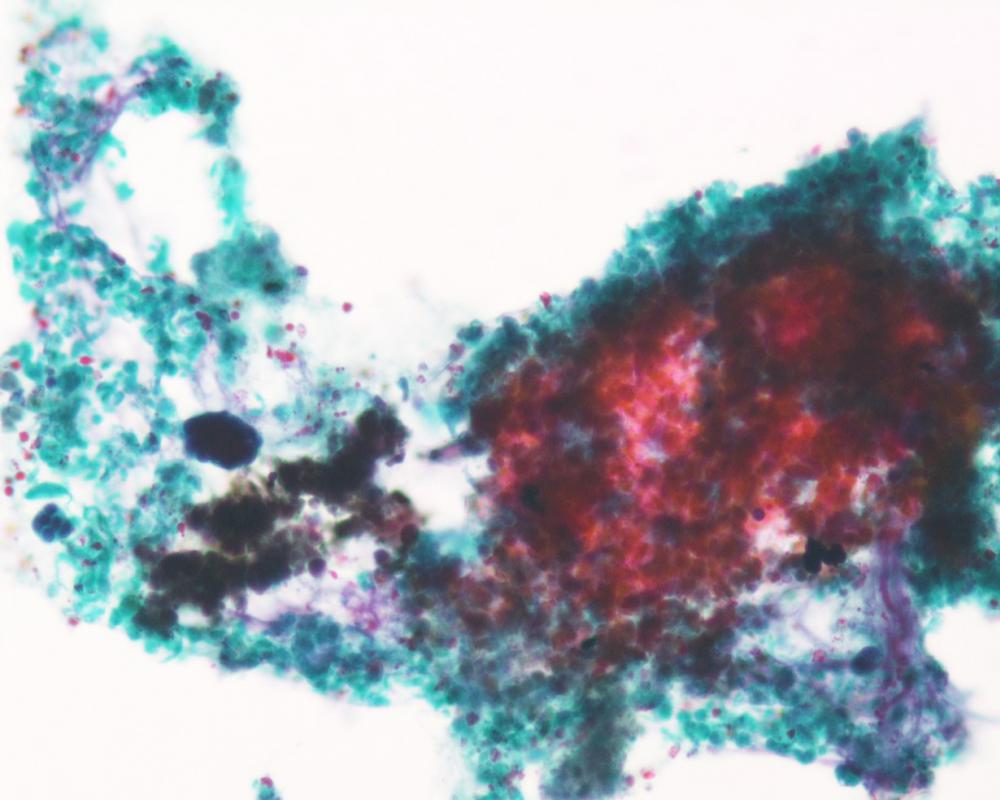

第35回日本臨床細胞学会九州連合会学会(宮崎)スライドカンファレンス症例4

種別:婦人科

出題:熊本大学病院 病理診断科・病理部 佐野直樹 先生

| 年齢 | 60歳代 | 性別 | 女性 |

| 採取部位 | 子宮頸部 | 採取方法 | 擦過 |

臨床所見

既 往 歴:糖尿病、脂質異常症

現 病 歴:4年前に帯下の増加を自覚し受診し、子宮頸部細胞診でNILMの判定。今回、下腹部痛を主訴に受診し、腟鏡診では病変は不明瞭だったが、双合診で子宮頸部全体に硬結あり。

| 正解 | 5.胃型粘液性癌 |

▼選択肢及び投票結果

| 1.化生細胞および修復細胞 | 3件 | (3.1%) | |

| 2.重層性粘液産生上皮内病変(SMILE) | 38件 | (39.2%) | |

| 3.通常型腺癌 | 10件 | (10.3%) | |

| 4.明細胞癌 | 26件 | (26.8%) | |

| 5.胃型粘液性癌 | 20件 | (20.6%) | |

| 投票総数 | 97件 | (100%) |